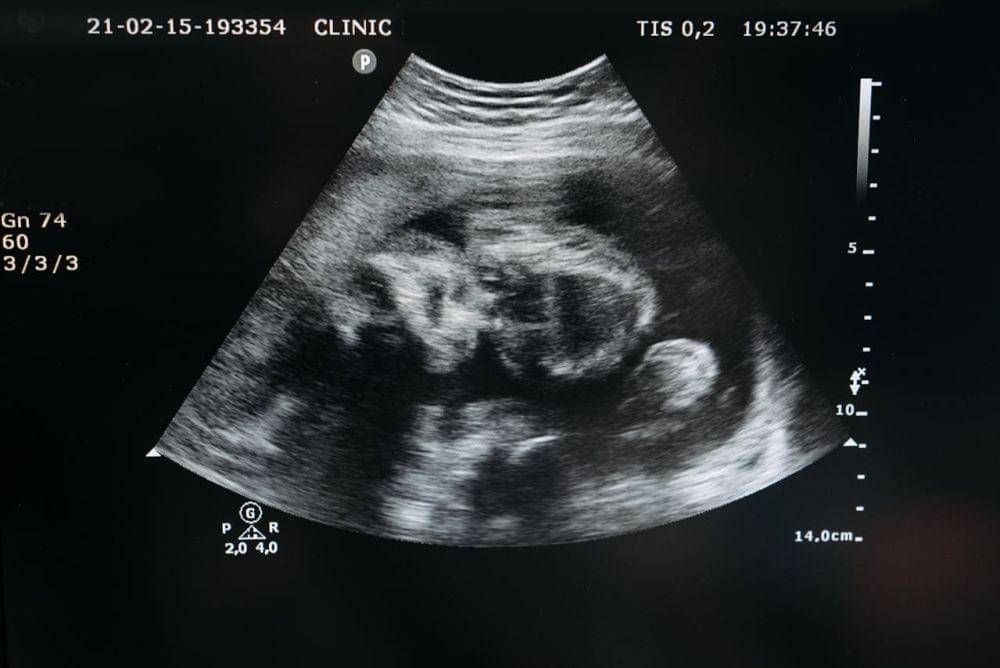

Terdapat sebuah penelitian pada 2005 yang menemukan bahwa janin bisa menangis di dalam kandungan sejak kehamilan masuk usia 20 minggu.

Namun, tangisan janin tidak bersuara dan tidak seperti bayi yang sudah lahir, Ma. Tanda janin menangis diantaranya yaitu menjulurkan lidahnya serta membuka dan menggerakan mulutnya.